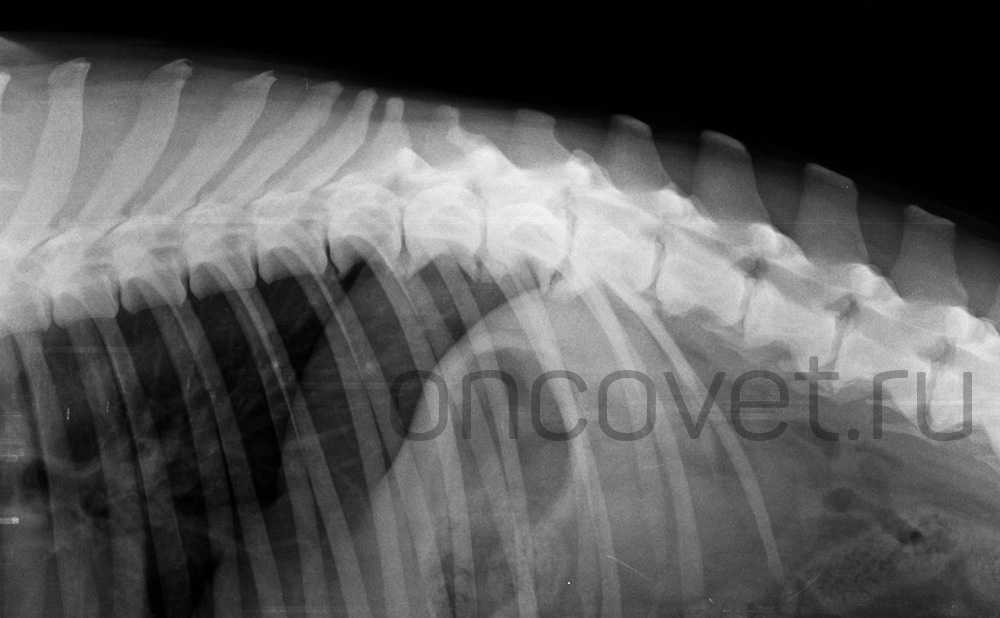

При рентгенографическом исследовании характерными признаками дискоспондилита будут являться сужение межпозвонковых пространств, деминерализация иэрозированиесубхондральных пластинок, неравномерность замыкательных пластинок, разрастание костной ткани с образованием спондилофитов, вплоть досращения позвонков. Может наблюдаться расширение межпозвонкового пространства и эрозия тел позвонков.

Рис. 2. Дискоспондилит у собаки Th9- L4.

Компьютерная томография — более подробное исследование костной ткани, признаки будут те же, как при рентгенографической диагностике.